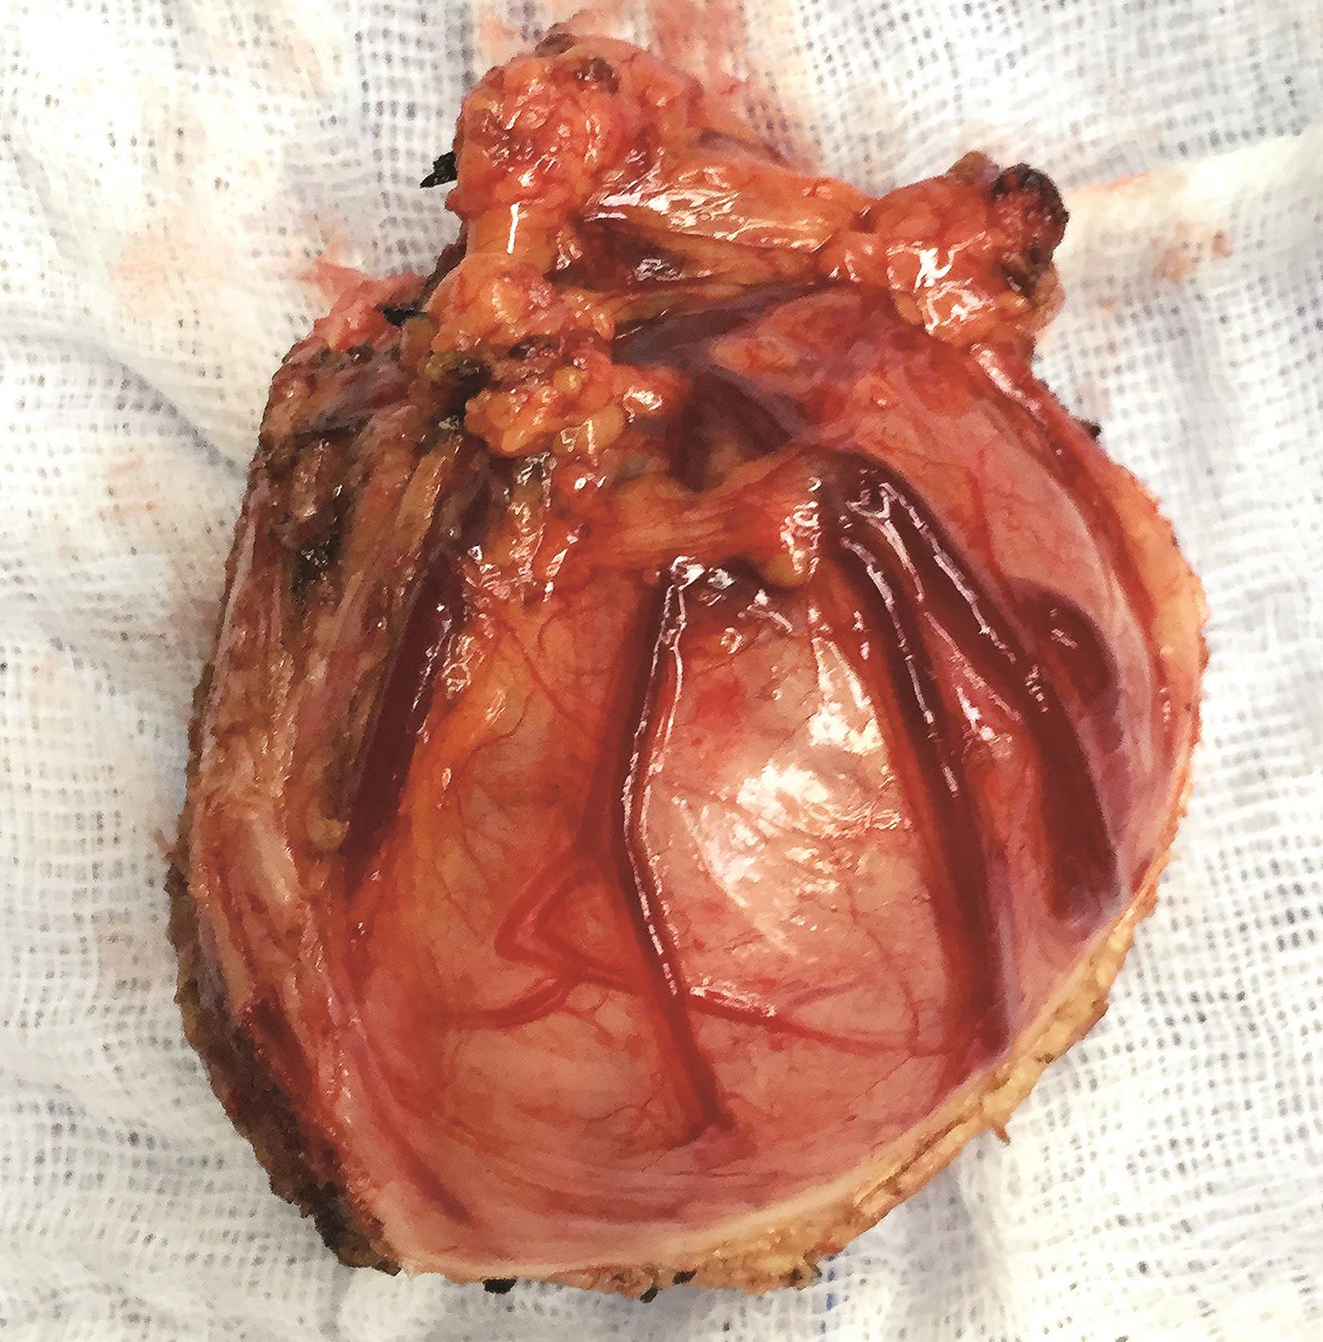

图7 手术切除标本大体观

患者于2018年08月30日接受“腹腔镜+胃镜双镜联合胃肿瘤切除术”,胃肠外科与消化科医师共同上台。术中内镜见胃体小弯侧后壁直径4cm黏膜下肿瘤,腔内生长,未侵犯胃黏膜及浆膜(图3),胃周淋巴结无肿大,小网膜囊内可及直径1cm钙化脂肪结节一枚,肝脏、盆腔、腹膜未及转移灶。经口置入内镜,探查肿瘤,于肿瘤边缘黏膜下注水(图4);内镜指引下,腹腔镜下以超声刀距肿瘤边缘1cm切开胃壁浆膜,沿肿瘤包膜外,全层切开胃壁,完整切除肿瘤(图5);以3-0可吸收线间断全层缝合胃壁缺损;术中胃镜检查胃创面;创面部分黏膜缺损处内镜下以钛夹封闭(图6);肿瘤标本置于标本袋内,经脐部戳孔处取出(图7)。

病理诊断:GIST(4.0cm×3.0cm×2.5cm),核分裂象<5个/50HPF。脂肪坏死纤维化结节。